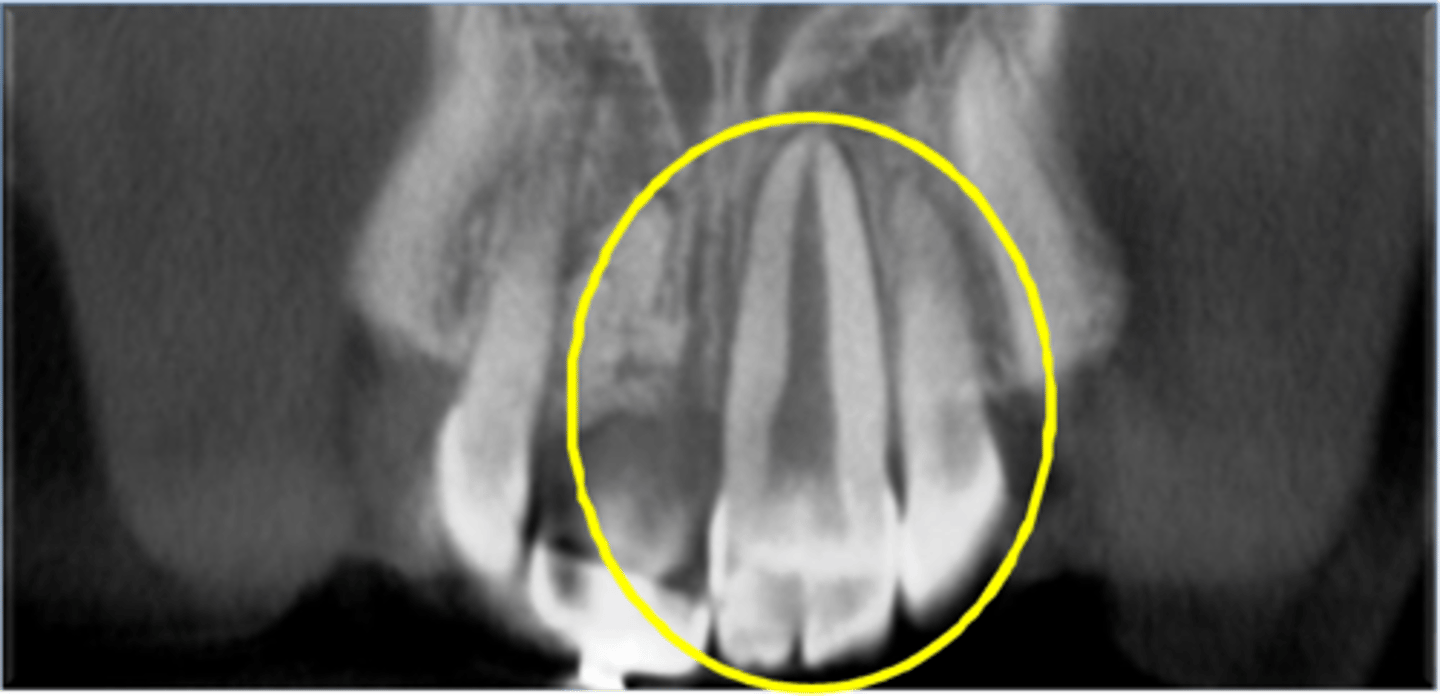

Characteristics of Fusion?

Missing tooth, 2 pulp chambers

Characteristics of Gemination?

1 pulp chamber, tooth bud development

Gemination common in?

What is Concrescence?

Fusing of teeth at cementum